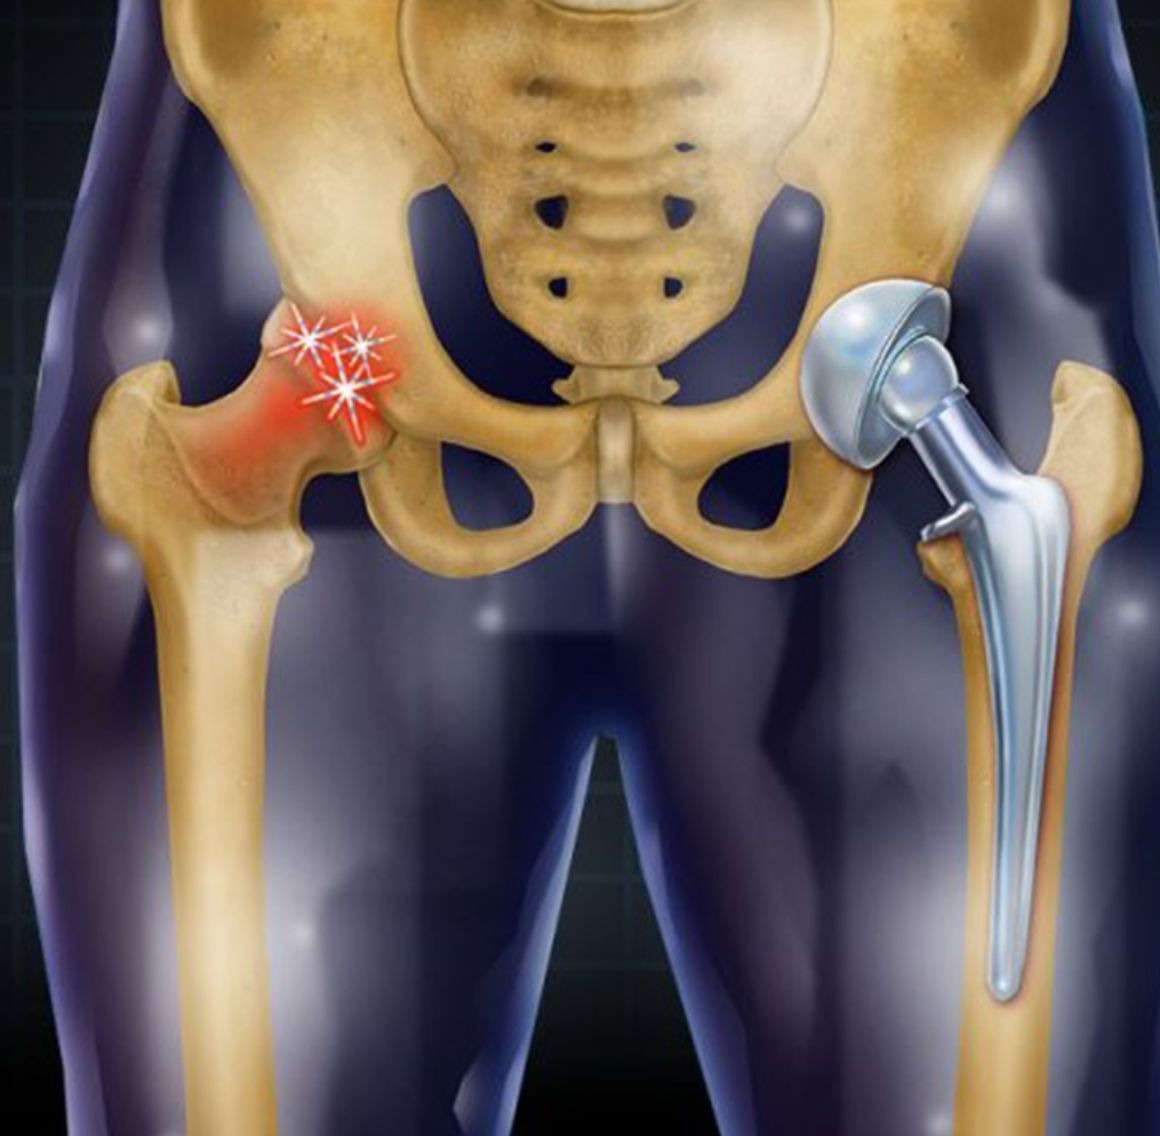

Hip Replacement Surgery involves removing the damaged or worn portions of the hip joint and replacing them with artificial components. This advanced procedure is designed to relieve chronic pain, improve mobility, and enhance overall quality of life. It is highly recommended for patients suffering from severe arthritis, hip fractures, or other debilitating hip conditions that do not respond to conservative treatments.

Common Indications: